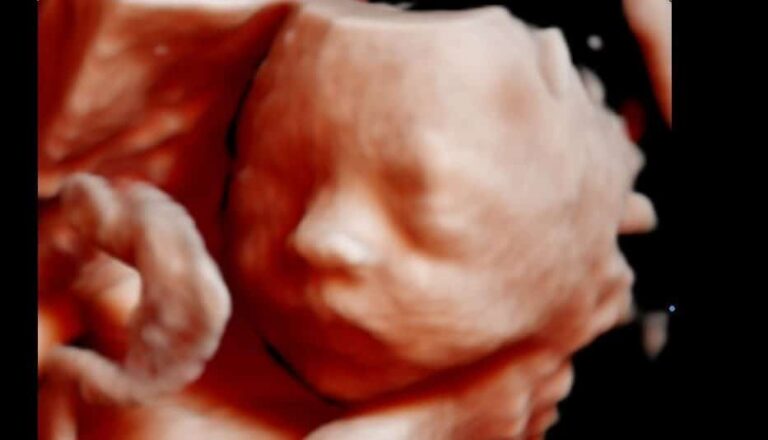

O que é ultrassom 3D ou 4D?

O método de ultra-sonografia 3D (três dimensões) é uma inovação do método 2D, transforma as imagens convencionais em…